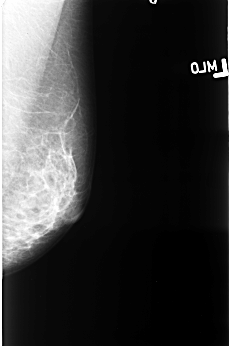

B_3403_1.RIGHT_CC

LEFT_CC LINES 4584 PIXELS_PER_LINE 2968 BITS_PER_PIXEL 12 RESOLUTION 50 NON_OVERLAY